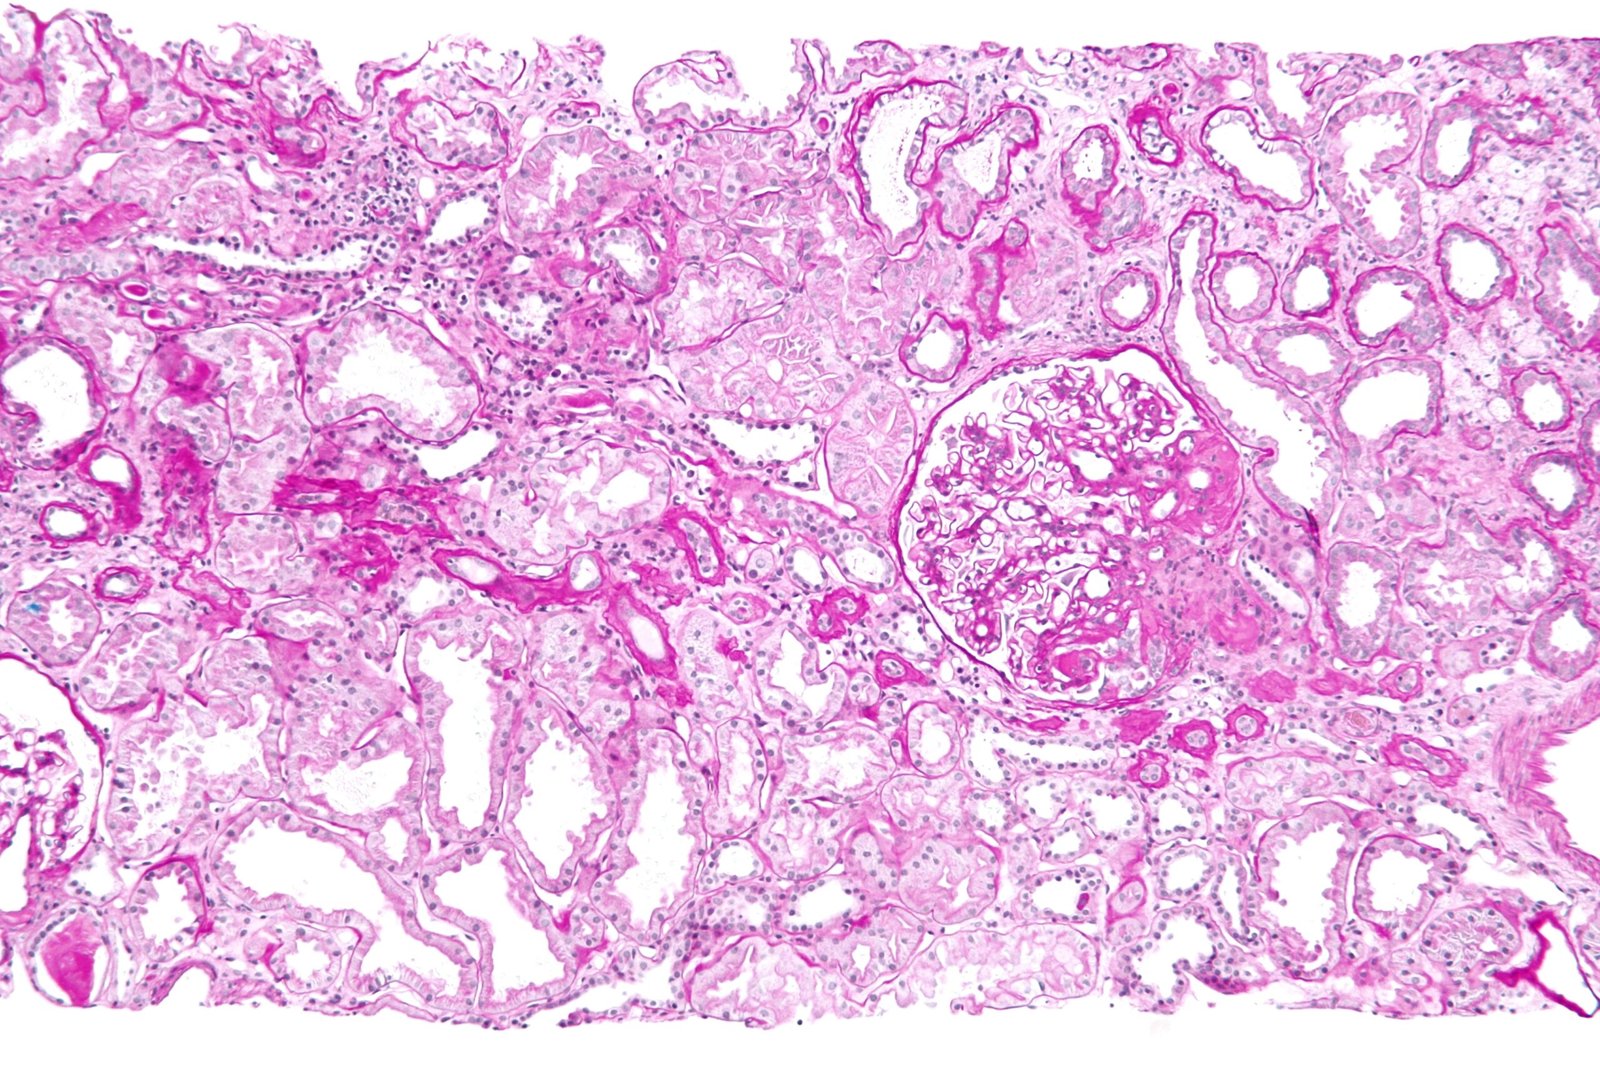

Once obtained, the biopsy sample is divided for multimodal analysis, yielding a definitive diagnosis in 95% of cases. Light microscopy (LM) examines paraffin-embedded sections stained with hematoxylin-eosin, periodic acid-Schiff (PAS), silver, and Masson’s trichrome, revealing glomerular, tubular, interstitial, and vascular changes. For example, it distinguishes proliferative from sclerosing glomerulopathies. Immunofluorescence (IF) on frozen sections detects immune deposits using antibodies against IgG, IgA, C3, etc., crucial for immune-mediated diseases like IgA nephropathy (Berger’s disease) or membranous nephropathy. Electron microscopy (EM) provides ultrastructural detail, identifying podocyte effacement in minimal change disease or subepithelial deposits in membranous glomerulopathy. Molecular techniques, like gene sequencing for hereditary nephropathies (e.g., Alport syndrome), are increasingly integrated.

Interpretation requires expertise from renal pathologists, correlating findings with clinical data. A typical report includes a semi-quantitative scoring system, such as the activity/chronicity index for lupus nephritis, influencing therapy. For instance, a biopsy showing crescentic glomerulonephritis might prompt urgent plasmapheresis and cyclophosphamide. In transplants, it detects antibody-mediated rejection via C4d staining. Limitations exist: sampling error (e.g., missing focal lesions) affects 5-10%, and artifacts from processing can mislead. Artificially intelligent tools are emerging to enhance accuracy.